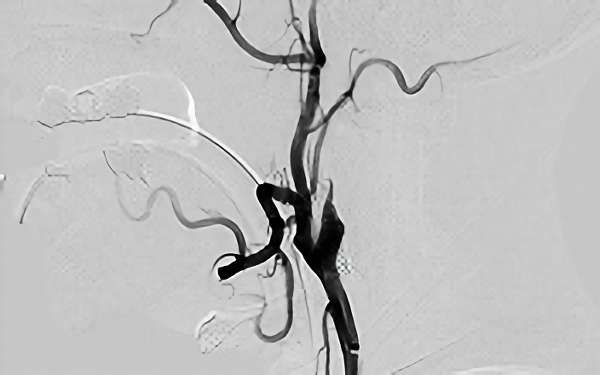

177

'18年7月10日

左内頚動脈狭窄症

70代

院内外来

手術写真

治療

前

中

後

手術日